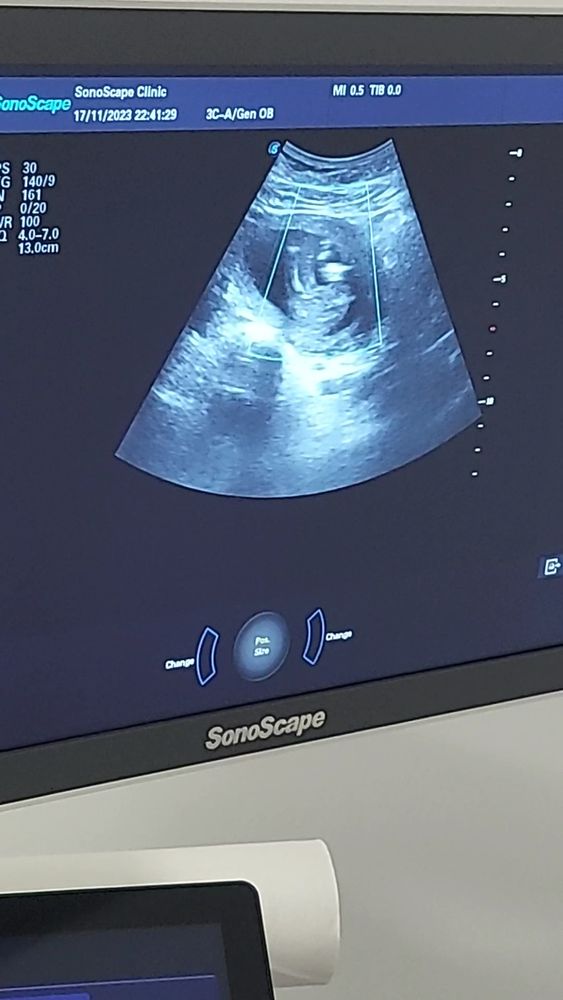

Сегодня узнаем кто в домике живет) (много фото узи) а вы как думаете?)

Плохое качество фото, видно что все они сняты между ног, но не чётко, вообще яичек нет вроде бы, значит девочка.

УЗИ 12 недель Точно девочка?)